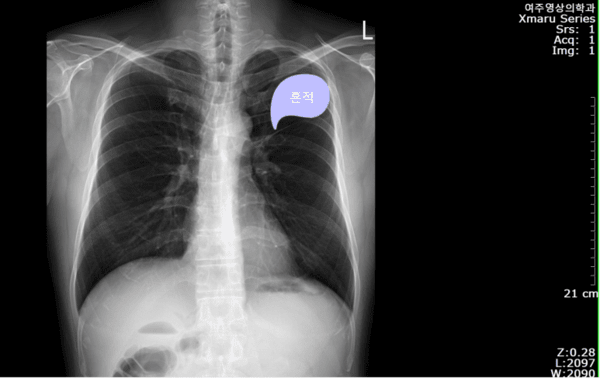

"주님! 저에게 결핵을 주소서! 그리고 제가 주님의 능력으로 치료를 받게 해 주소서! 이러한 치유의 기적을 보고, 부모님이 예수님을 알게 해 주세요! 예수님이 하나님의 아들이시며, 살아계신 분이심을 알게 해 주십시오. 죽어가는 아들을 위해서 예수님께 나올 수 있는 부모님이 되게 해 주십시오."

나는 하나님의 약속의 말씀을 믿고 끝까지 부모님의 구원을 위해서 기도했고, 주님은 신실하게 응답해 주셨습니다. 지난 2018년 종합검진을 받을 때, 아래와 같은 소견서를 받았습니다.

소견서를 받은 후, 예전에 기도했던 사실이 생각나며, 다시 한번 신실한 하나님을 생각하는 시간을 가졌습니다.